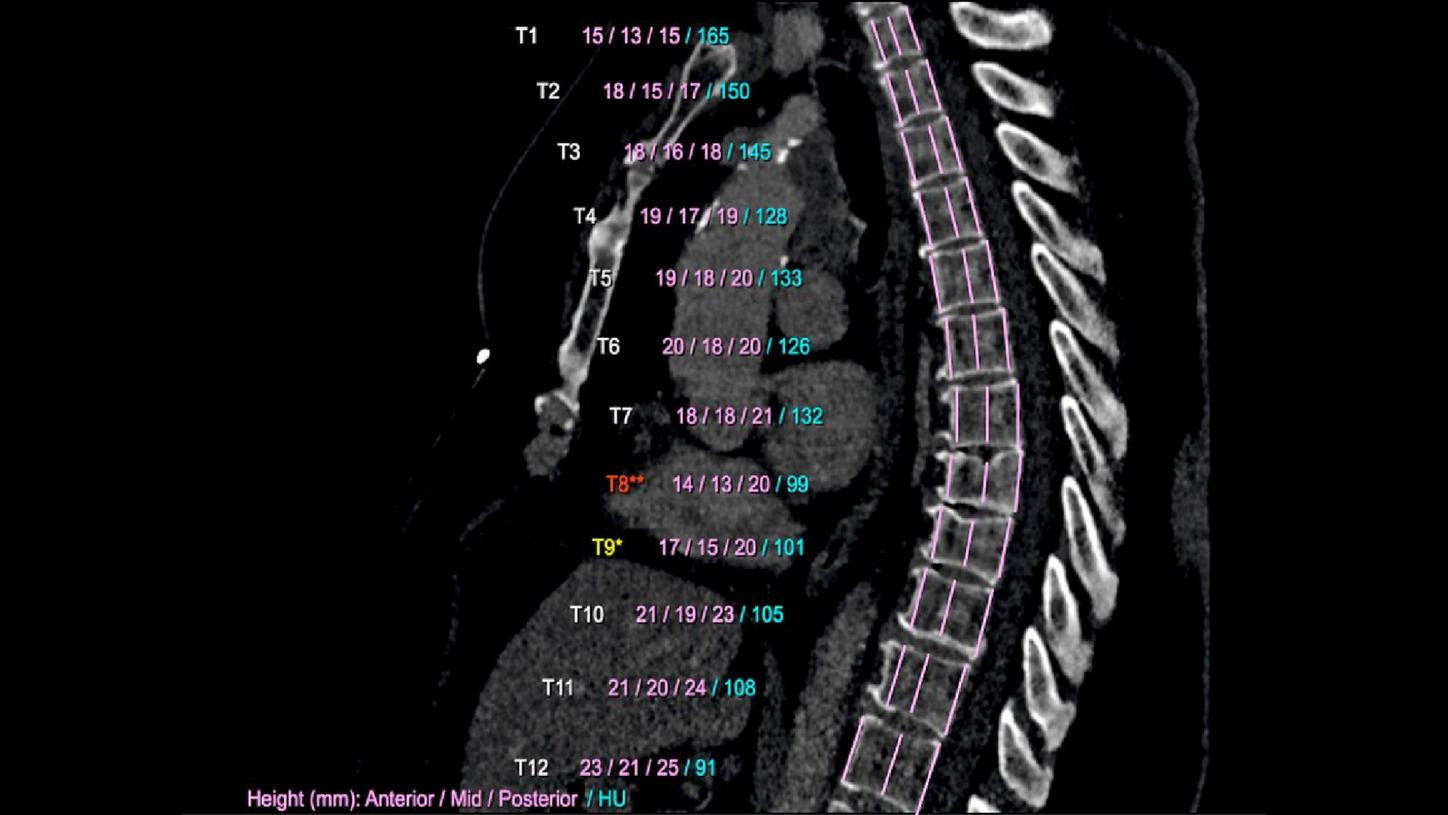

Computed Tomography is moving beyond its traditional diagnostic role to become a key player in early disease detection and therapy planning. This expansion means an even broader patient cohort and resilient productivity demands. You need a reliable partner with products, services, and the infrastructure to support new business models and prioritize environmental sustainability and robustness. Computed Tomography at Siemens Healthineers, with its legacy of listening for almost 50 years, is innovating ahead of these developments, even before potentials become needs.